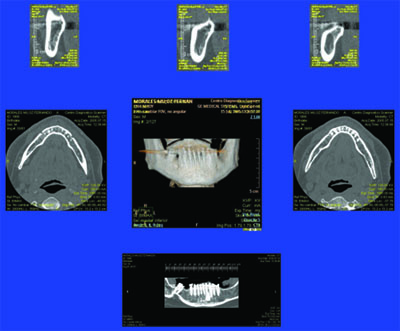

Es frecuente la remisión de pacientes a los que se les ha intervenido parcialmente, en base a sus requerimientos, olvidando los conceptos básicos de la fisiología normal del SEG(Sistema Estomatognático), y que terminan siendo motivo de una Rehabilitación Oral Integral , que debió ser concebida desde el principio de su tratamiento. Se presenta a la consulta un paciente derivado, portando dos puentes recientes de porcelana, con severas anomalías en su oclusión, aquejado de síntomas dolorosos en varias piezas dentarias, sobre todo a los cambios de temperatura y demás estímulos locales. Estudiado el enfermo radiográficamente, procedemos a desmontar los puentes encontrando debajo de uno de ellos un gran proceso carioso por filtración de la corona. Tallamos ambos maxilares y montamos un conjunto provisional a partir de un sencillo encerado realizado en clínica, el que usamos como férula radiográfica instalando en los sectores a implantar conos de gutapercha. Obtenemos imágenes de Dentascan Y procedemos a implantar mediante técnicas de Cirugía Minimamente Invasiva y Semi Sumergida y se toman impresiones mediante transfers intra operatoriamente. Realizamos un control mediante ortopantomografía. Mientras tanto se realiza en laboratorio un encerado para la confección de provisionales correctos. Dos meses después, se verifica la salud peri implantaria Y se instalan los nuevos provisionales sobre los abuttments ya construidos y los muñones tallados. Inmediatamente procedemos a tomar impresiones definitivas y contruir los núcleos de porcelana de alta densidad de la Guía Anterior (QUE ES LO PRIMERO QUE DEBEMOS RECONSTRUIR) y probarlos en boca para luego terminar la Guía Anterior y observar su adaptación y estética, para finalmente construir los cuadrantes posteriores y comprobar las disclusiones.